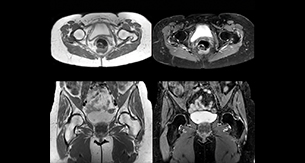

Add fat suppressed imaging without time penalty for peripheral joints

“In peripheral joints, mDIXON TSE imaging aids in diagnosing injuries in ligaments or tendons, for imaging degenerative and inflammatory pathologies such as osteoarthritis and rheumatologic disorders and for oncological exploration.”

“For tendon and ligament assessment around knee, ankle, hip and elbow, mDIXON TSE contributes to diagnostic confidence thanks to having images both with and without fat suppression – and without time penalty. This is possible because 2-point mDIXON is faster than the common 3-point Dixon method. It can also increase efficiency as it helps avoid having to add scans during the exam.”

Amazing quality of fat suppression

“In peripheral joints, we get good image quality in difficult areas with mDIXON TSE.

Fat suppressed images appear homogeneous over the entire image, even with large coverage at 3.0T – for instance in scapular or hip girdles – or in the bearing areas or around metal prostheses, where fat suppression is often deficient with STIR or spectral fat suppression, causing diagnostic difficulties. If a diagnostic image is right the first time, we don’t need to repeat or add a sequence.”

“mDIXON TSE sequences allow simultaneous characterization of morphological changes from the in-phase T2-weighted images and visualization of edematous changes, thanks to the water T2-weighted images from the same acquisition. Anatomical and morphological considerations could be a partial or complete ligament tear, a bony avulsion or hematoma.”

“For soft tissue assessment mDIXON brings similar benefits. For example in one T2-weighted mDIXON TSE acquisition, having the multiple contrasts helps us assess abnormalities in peripheral nerves fascicles, which may be due to anatomical or inflammatory changes..”